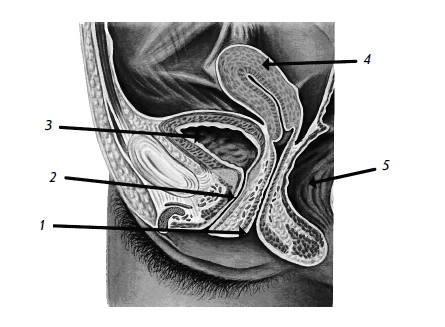

Женский мочеиспускательный канал (рис. 4) короткий и широкий (длиной 3–4 см, шириной 1–1,5 см) и близок к анальному (заднепроходному) отверстию. Такая близость анального отверстия и мочеиспускательного канала создает благоприятные условия для инфицирования мочевых путей бактериями из кишечника.

Рис. 4. Женский таз

1 – влагалище; 2 – мочеиспускательный канал; 3 – мочевой пузырь;

4 – матка; 5 – прямая кишка